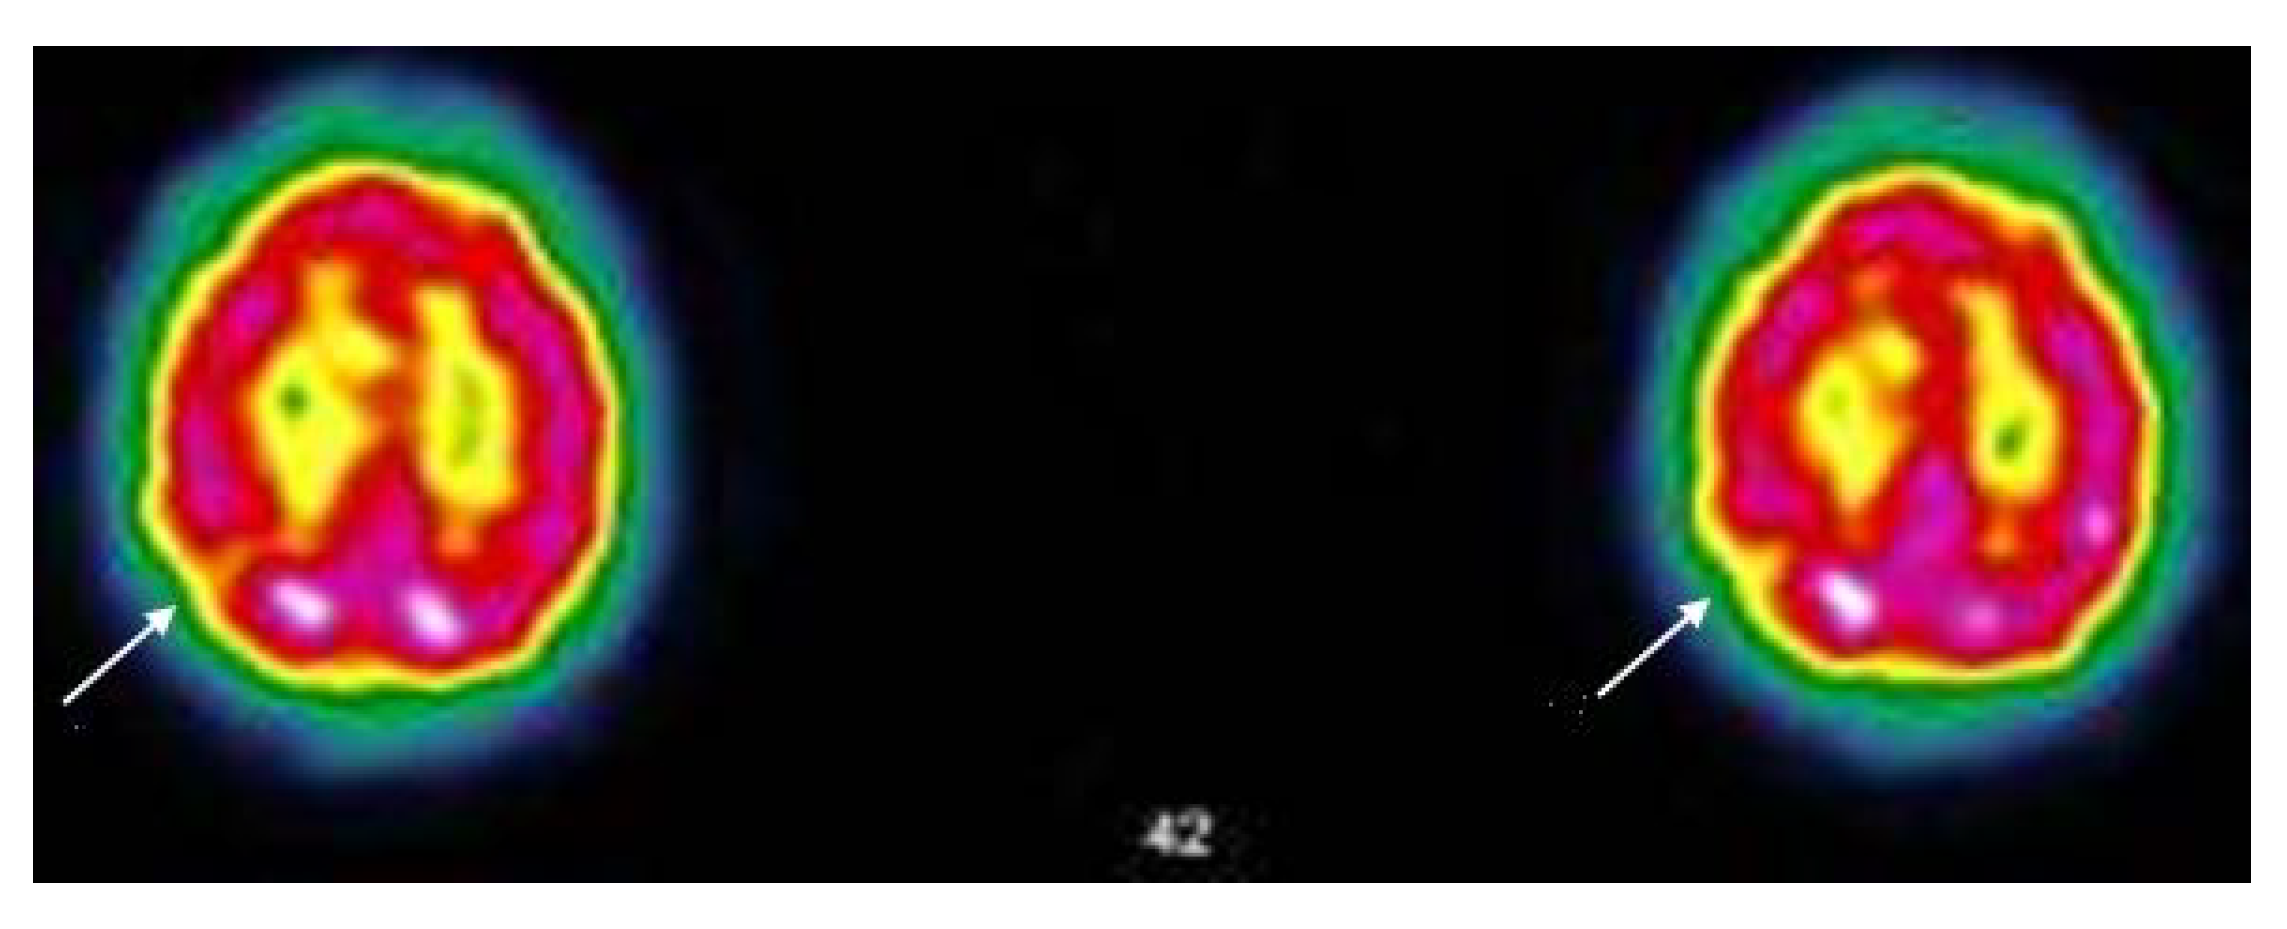

3.5. Narrative and SPECT-CT Images of Some Exemplary Cases

3.5.3. Patient MGA005

3.5.4. Patient MGA058

| 13 October 2020 Throat pain, rhinorrhea, bad aches, severe fatigue and headache, but no breathing difficulties, dysgeusia, anosmia. Stays at home, cured after 12 days. Home care only | 11 November 2020 Pain in both eyes, ocular pruritus, rapid ocular fatigue, noise intolerance, memory loss (forgets to pick up her daughter at school), concentration problems, remains isolated in her room, dyspnea at the slightest effort and at speech, almost continuous osteoarticular and muscular pains often with headaches, abnormal dreams, depressive feeling, fatigue, post-exertional malaise (PEM) | 27 July 2021 “On the images taken, left fronto-parietal, left frontal and left thalamic hypofixation is observed. No preservation of the sensory motor cortices. The fixation in front of the cerebellum is correct. Conclusion: Scintigraphic examination compatible with a cerebral pathology of the vascular type with clearer left fronto-parietal, left frontal and left thalamic vascular disorders”. |

| 3 March 2021 Cough, aching, elevated temperature, headache, 20 days in bed, loss of taste, loss of smell, severe tinnitus, 20 days in total. Home care | 5 October 2021 Hearing loss in right ear, balance always disturbed, dizziness, loss of vision, quickly tired, severe weight gain, quickly out of breath, became depressed, pain in left hip every night, post-vaccinations headaches, memory loss, word retrieval deficit, repeats herself and doesn’t realize it, forgets which groceries she went to get, has trouble concentrating, disseminated myalgia, insomnia, loss of sense of direction | 17 November 2021 “Heterogeneous tracer distribution throughout the cortex, with more marked hypofixation in the bilateral predominantly left superior parietal, left parietal, bilateral medial temporal and bilateral predominantly right parieto-occipital areas. Diffuse subcortical periventricular hypofixation. The basal ganglia and cerebellum show preserved and symmetrical tracer uptake. Scintigraphic image suggestive of vascular damage in the broad sense.” |